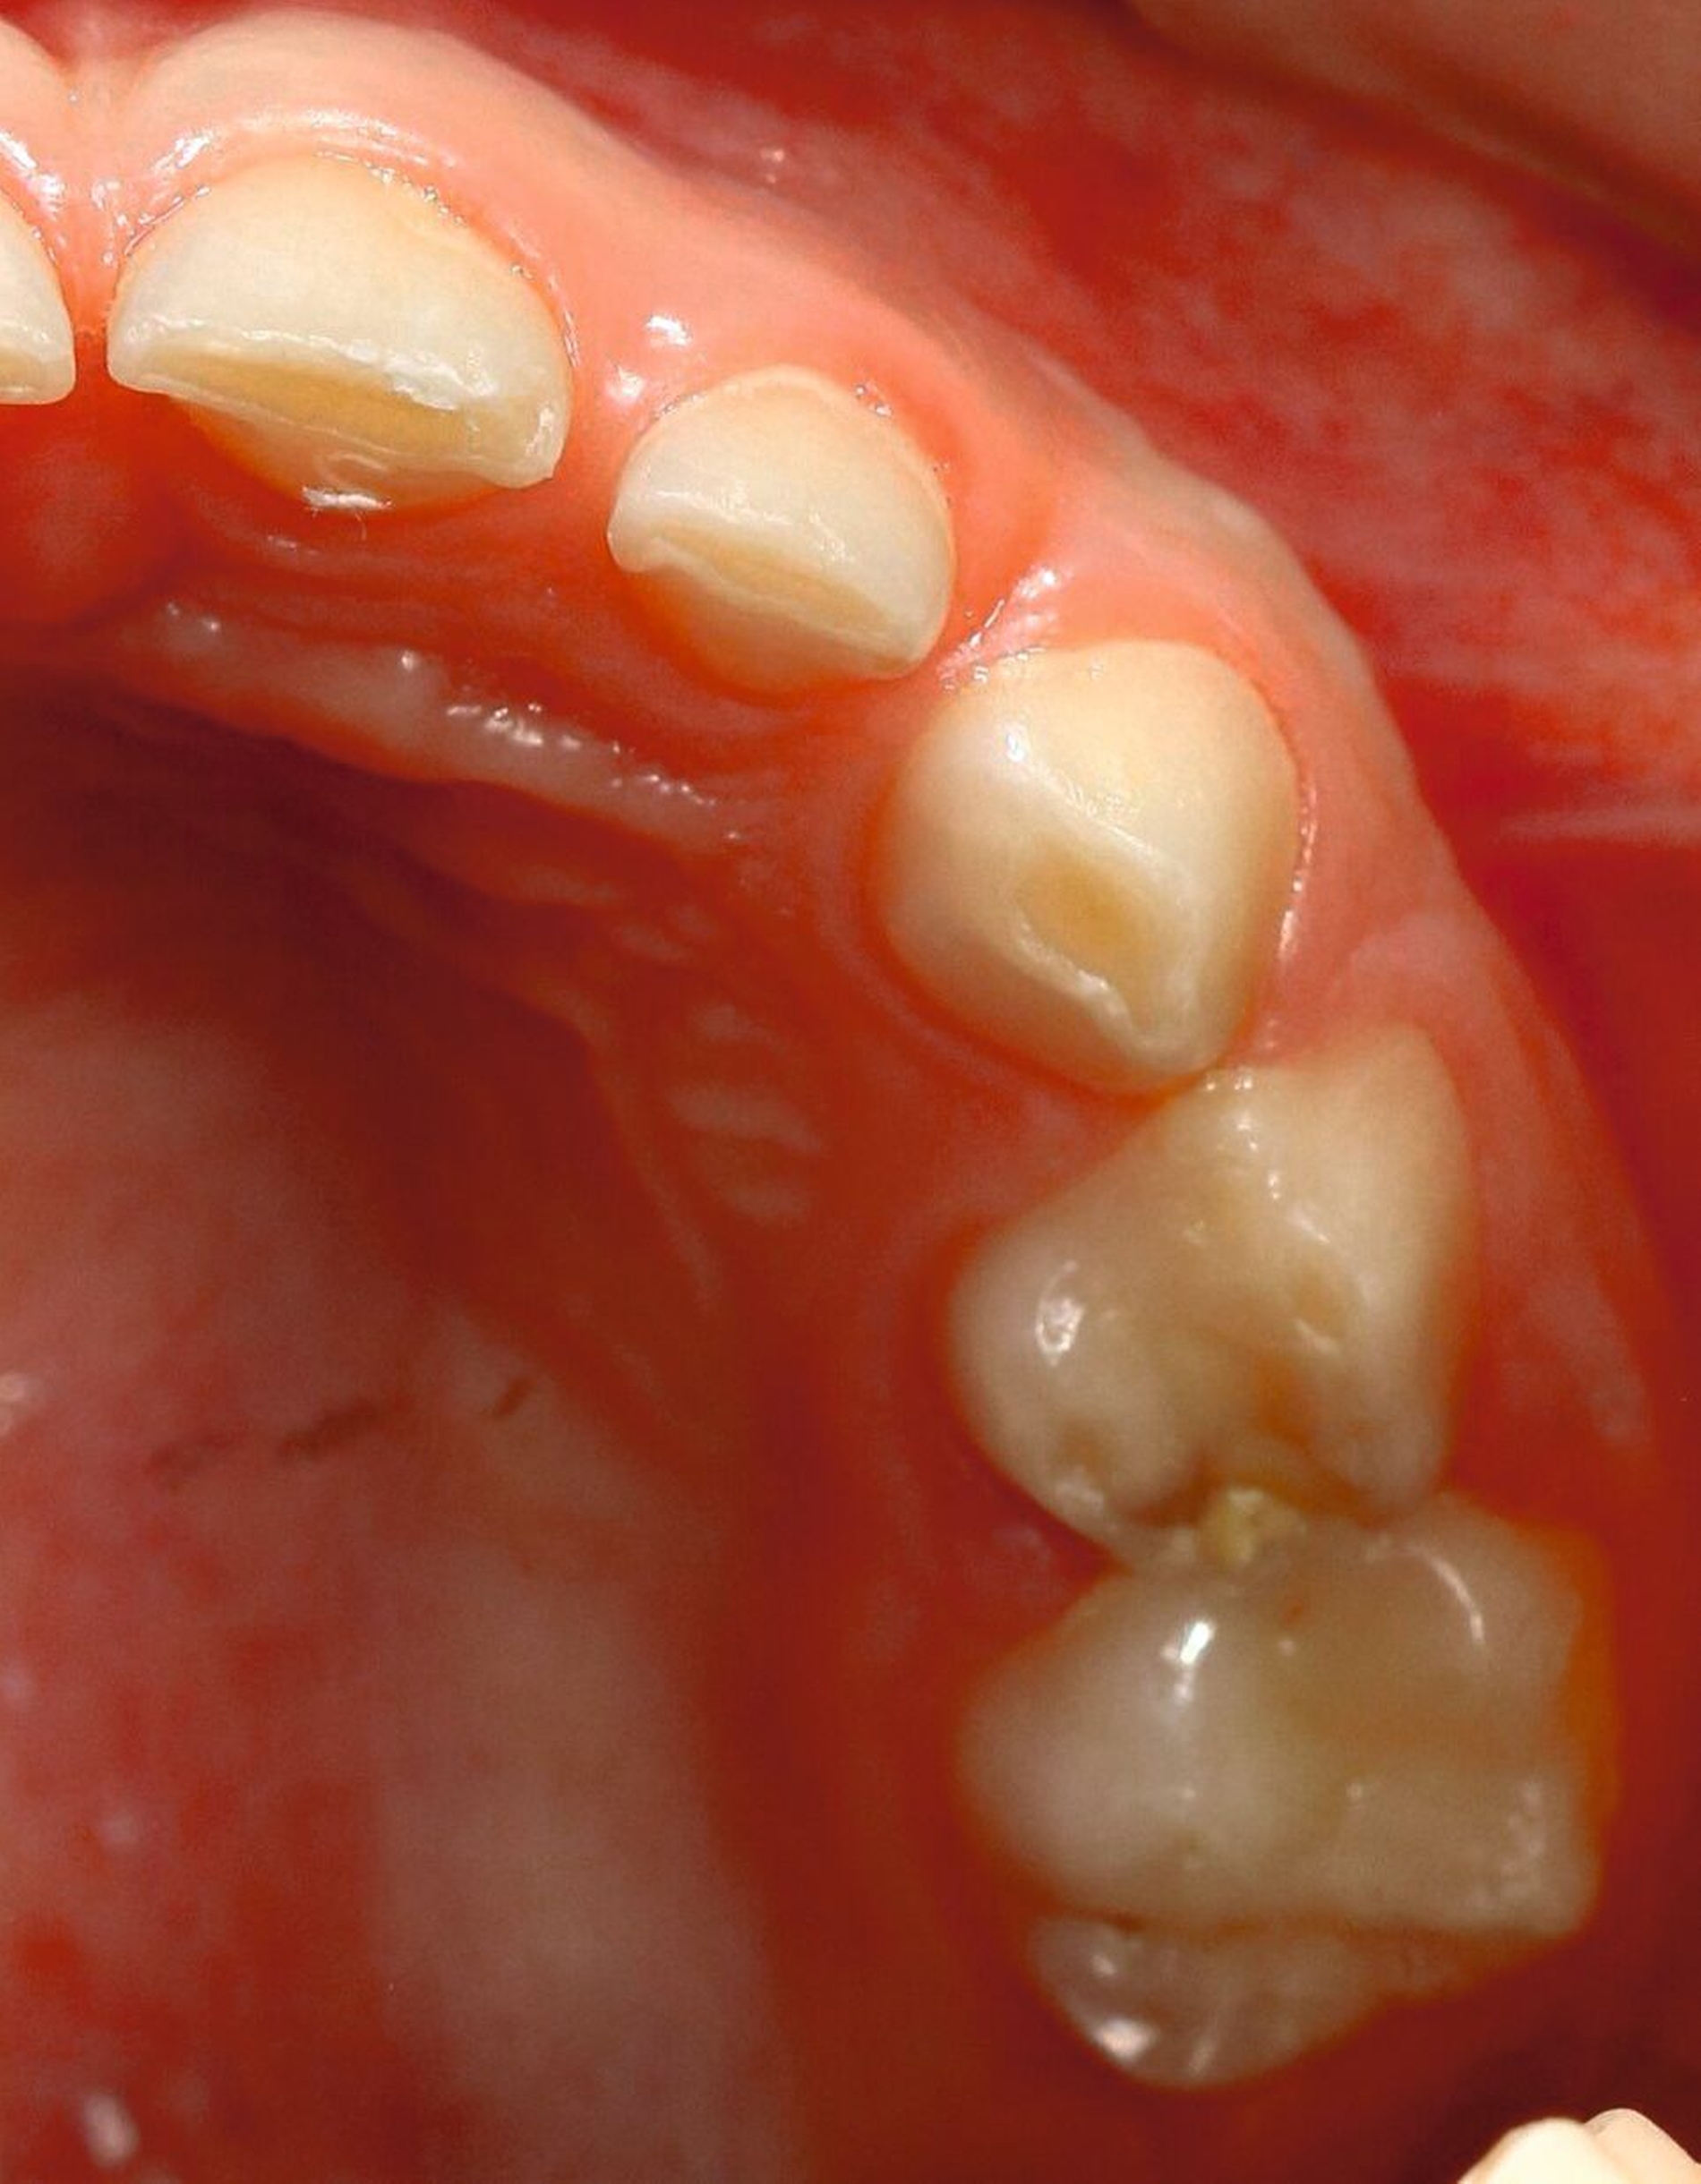

Nicht zuletzt können auch morphologische Gegebenheiten eine ausschlaggebende Rolle in Bezug auf Bruxismus spielen. So können gewisse Zahn- und Kieferfehlstellungen Attritionen fördern, wie dies zum Beispiel beim Kopf- oder Deckbiss der Fall ist (Abbildung 5), während andererseits große vertikale Abweichungen oder sagittale Stufen selten zu klinischen Bruxismuszeichen führen, weil die Zähne nicht in Okklusion stehen. Dies ist meist recht einfach zu diagnostizieren.